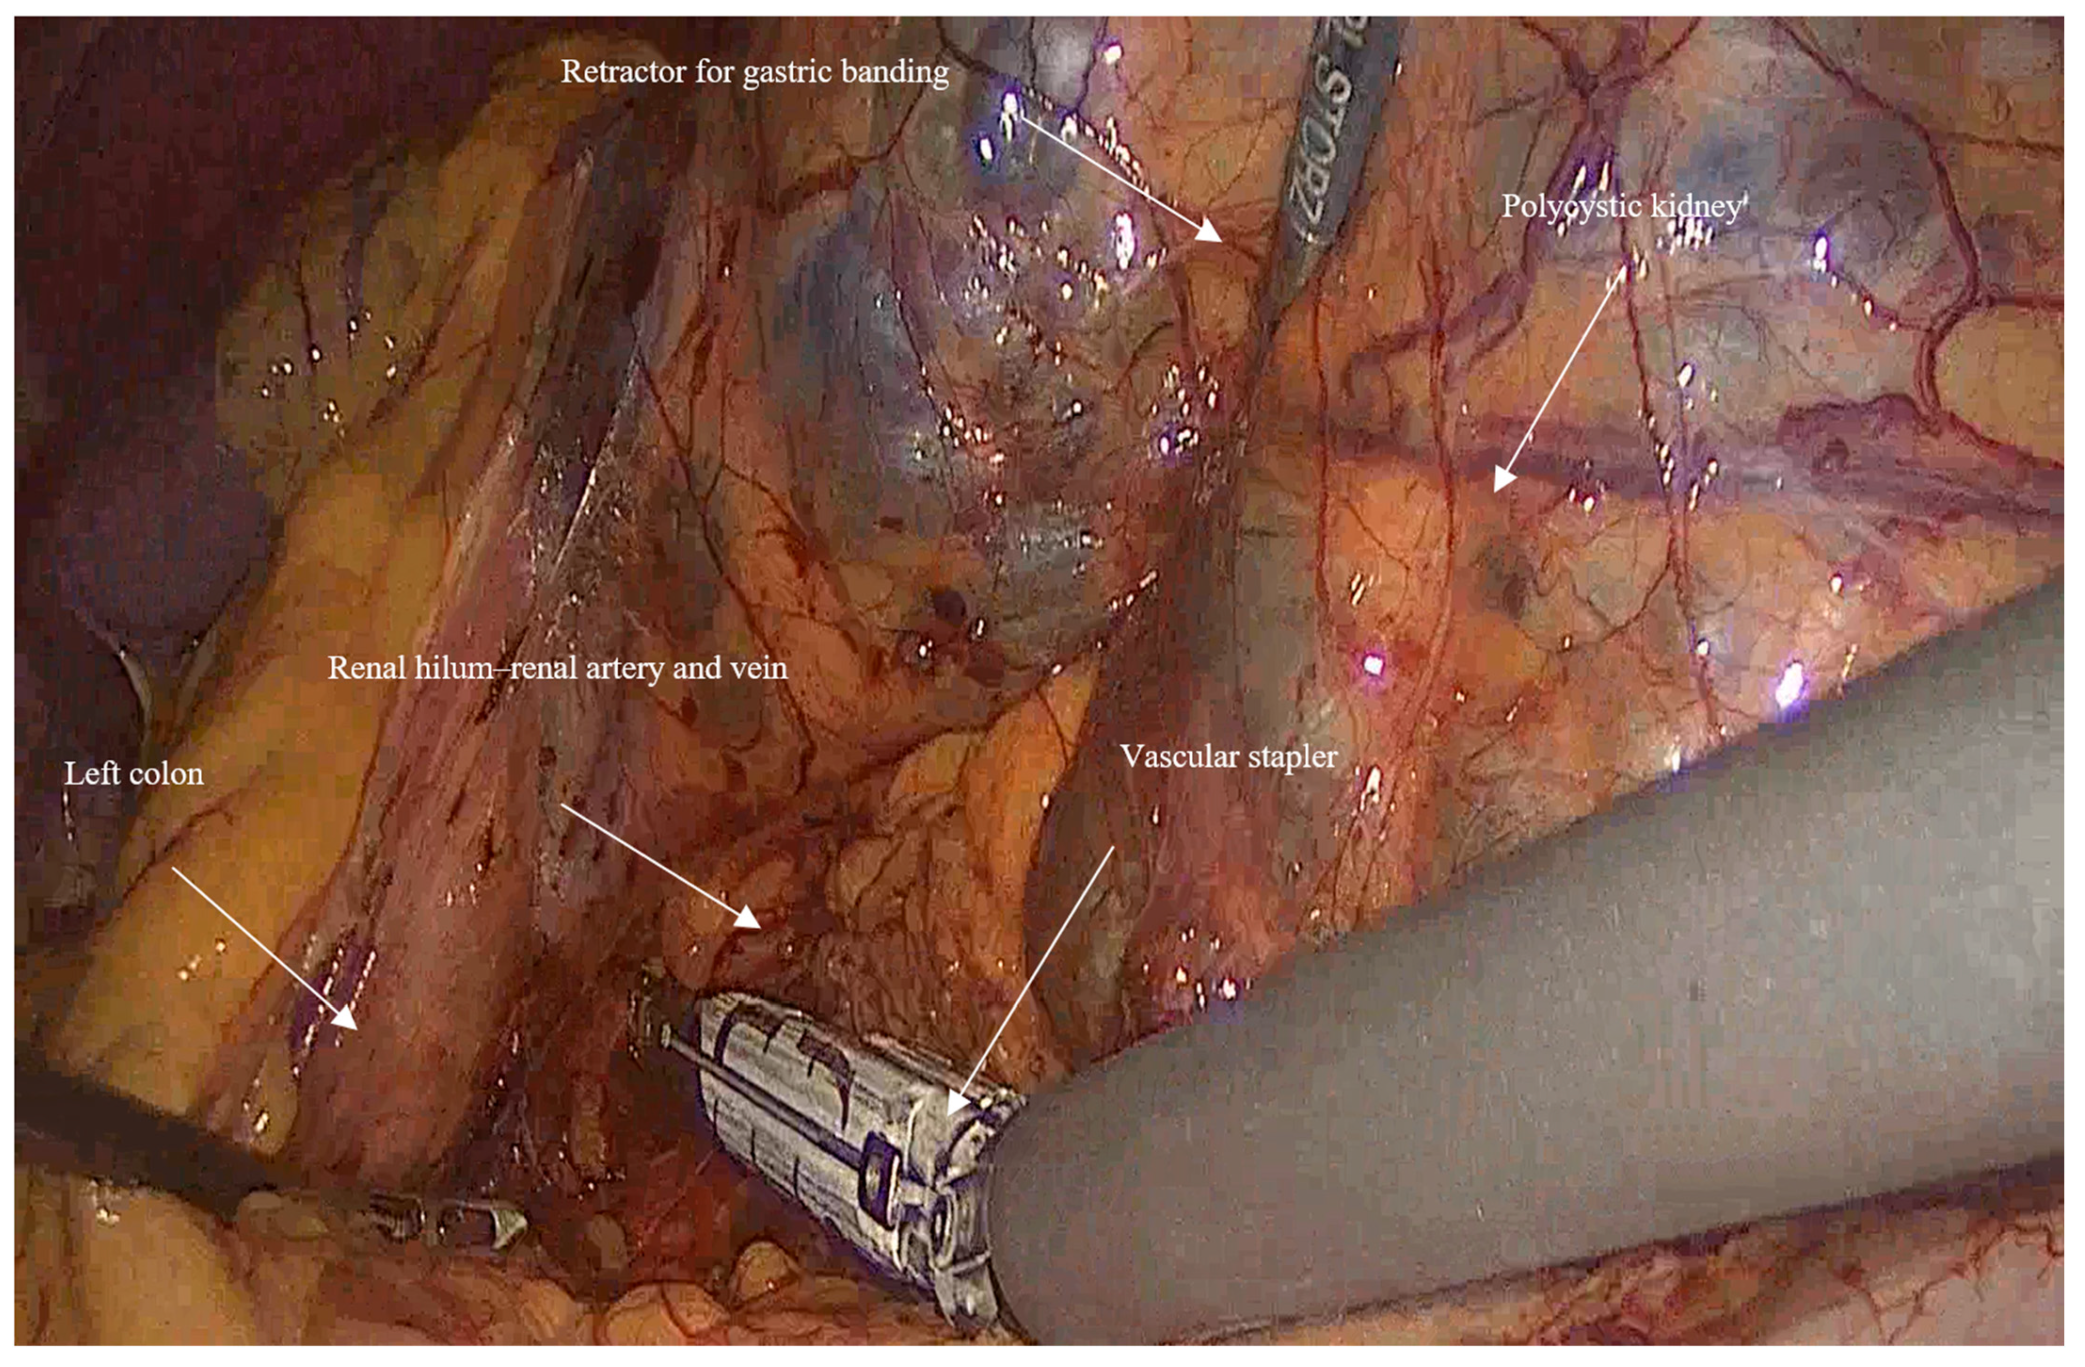

- In huge kidney with previous infections where controlled aspiration may be hazardous, a sufficient retraction with a retractor for Gastric Banding (Karl Storz 30,623 GB), which has a 0-to-90-degree angle of its tip and can provide an efficient retraction and elevation of the huge kidney from the psoas muscle and assist in gaining access to the hilum of the kidney (Figure 3).

- Mobilization: Initially, the left colon was mobilized laterally, and Gerota’s fascia was identified. Careful dissection was performed to reveal the kidney Figure 1.

- Vascular control and ligation: The renal artery and vein were clamped together close to the hilum of the kidney using a vascular stapler (SigniaTM with Tri-StapleTM reinforced reloads, Medtronic, Minneapolis, MN, USA). Following that, a dissection of the rest of the inferior border of the kidney is completed, and then the ureter is ligated using Hem-o-lock™ clips (Weck, Research Triangle, NC, USA; Figure 2).